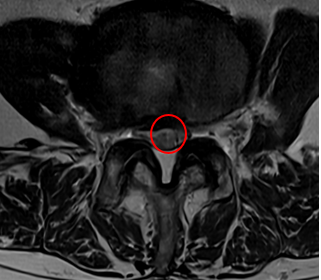

腰椎MRIで画像検査をしたところ、赤い枠で囲った箇所(L3/4)に椎間板ヘルニアができていました。

術後から2週間後には腰痛、右お尻から足にかけての痛み・痺れともに10点から2点に軽減したとのことです。術後のMRIでは椎間板ヘルニアが減少して小さくなっているのが確認できております。